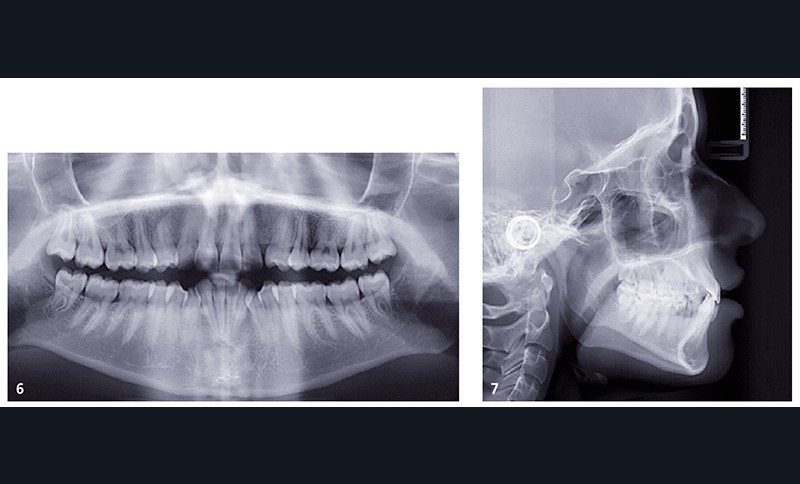

À l’examen de l’orthopantomogramme (fig. 6), le « signe du bouquet » confirme le diagnostic de DDM.